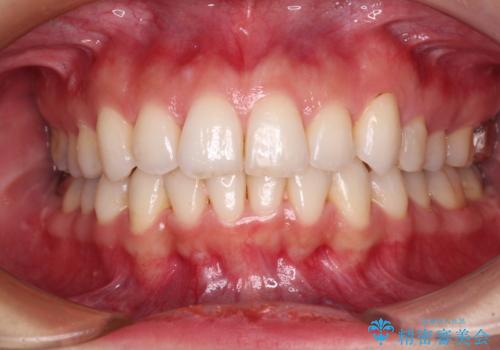

急速拡大装置で狭い歯列を骨格ごと改善 ワイヤー装置による矯正治療

- 下顎の前突感と前歯の叢生を気にして来院された患者様です。

急速拡大装置を用いて上顎骨を側方に拡大し、上顎の叢生を解消するとともに下顎歯列拡大により下顎の叢生も解消することとしました。

急速拡大装置使用直後は著しいスペースが正中に発現するため、ワイヤー矯正を行いますが、今回は治療期間を短くしたいとのことで、上下全体をワイヤー装置にて矯正治療することとしました。

上顎骨を拡大しない場合には、奥歯に咬みにくさが残ったり、下顎前歯の歯肉退縮や口元の突出感などが出たりと、妥協的な仕上がりとなります。